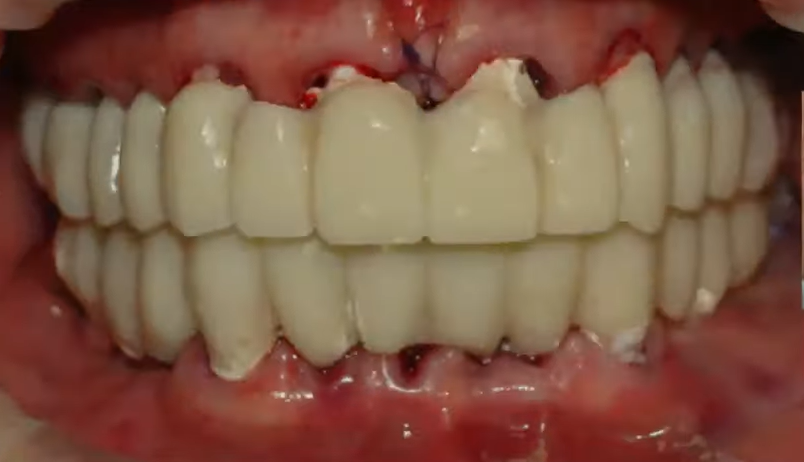

Temporary restoration of the upper and lower jaws placed on the day of implantation. YouTube / Dr. Kamil Khabiev / Dental Guru Academy

After three months, osseointegration was successfully completed, secondary stability was sufficient for the placement of a permanent restoration, and here is the result.